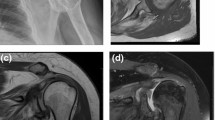

Table 1 demonstrates the results of evaluation of degenerative and trauma shoulders (4-part or Neer Type VI dislocated proximal humerus fractures). The Walch classification, which uses 2-dimensional (2D) axial computed tomography (CT) scans, assesses the glenoid and the position of the humeral head in relation to the glenoid in various degrees of osteoarthritis (Figs. 1, 2). Grade D in sample D2 indicates very severe arthritis with subluxation of the anterior humeral head, grade A1 in sample F2 indicates a well-centered humeral head with minor erosions.

The Hamada classification evaluates the radiological findings after a rotator cuff tear and shows the course of the rotator cuff tear arthropathies (from 1 to 5). Of the trauma specimens, F2 was rated IV/b and orthopedic specimens D1 and D2 were rated IV/a and V, respectively, indicating a poorer prognosis of arthropathy for the orthopedic patients.

The Outerbridge classification is originally based on arthroscopic findings, but in our study, we used MRI scans as an advanced imaging tool; Outerbridge 2 in the case of sample D1 indicates blistering swelling/fraying of the articular cartilage extending to the surface, a moderately damaged cartilage.

Meanwhile, the osteoarthritis score clearly demonstrated the presence of advanced osteoarthritis among the orthopedic indication specimens. In case of control samples, healthy tissue structure was confirmed by histological examination (Fig. 3).